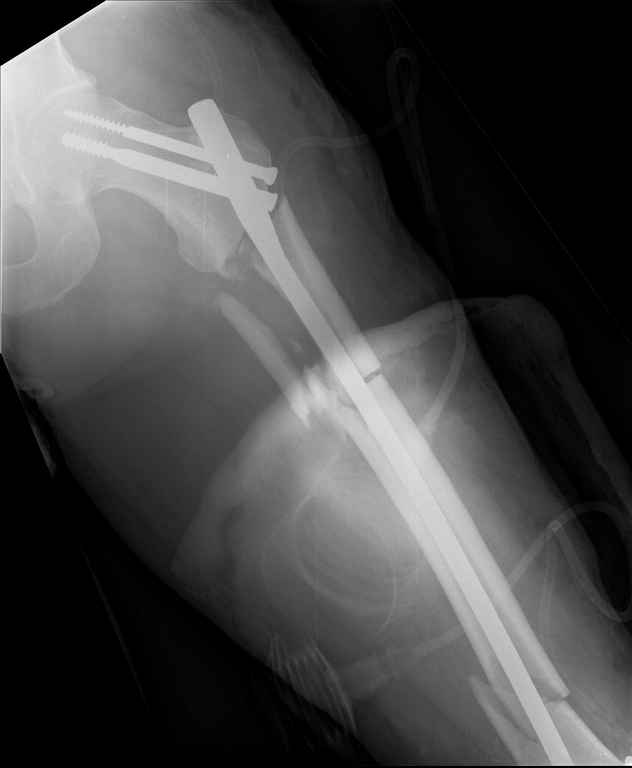

Ds: ТСТ. ЗЧМТ. СГМ. ЗТГК. О/фрагментарный перелом левого бедра. З/оскольчатый перелом с\3 левого плеча. Перелом левого локтевого отростка. З/перелом наружного мыщелка б/берцовой кости в/3 м/берцовой кости левой голени. при поступлении, ПХО раны левого бедра( рана 1х1см по наружной поверхности бедра в с/3) налажено скелетное вытяжение , и гипсовая лонгета на левую в/конечность. Находился в реанимации. 17.02.11 был прооперирован: БИОС левого плеча, о/синтез левого локтевого отростка по Веберу, БИОС левого бедра (длинная версия Fi-Can Sanatmetal диаметр 10мм), мыщелок голени трогать не стали.при остеосинтезе бедра возникли трудности при закрытй репозиции перелома в н/3, в связи с чем решили открыться внизу , отрепонировали без особого труда и выполнили блокирование во фронтальной плоскости 3-мя винтами + 1 винт спереди гвоздя (промазал). Убрал костодержатель, все нормально, контроль ЭОПом стояние отломков нормальное, зашились. На контрольной R-мме на утро выявлено вторичное смещение дистального отломка. Левая нога по сравнению со здоровой удлиннена до 2,5см( это за счет вальгусной установки гвоздя в проксимальном отделе, боялся свалиться на варус). Теперь думаем как поправить положение отломков в н/3, и зафиксировать так чтобы не съехало. Наше предложение расшиться в н/3 бедра, разблокироваться, перелом отрепонировать вновь и установить 1или 2отклоняющих винта в сагитальной плоскости, затем заблокироваться во фронтальной плоскости снова. Помогите советом, как выйти достойно из сложившейся ситуации. Заранее спасибо.

С моей точки зрения удлинение (если таковое имеется) произошло не за счёт вальгусной установки стержня. На контрольной рентгенограмме блокирующие винты точно расположены в шейке бедренной кости и в центре ротации головки. И даже если выбран стержень с максимальным из выпускаемых углом в 135 градусов, он не обеспечит столь значительного удлинения конечности. Увеличенный шеечно-диафизарный угол на контрольной рентгенограмме со стержнем объясняется наружной ротацией конечности при рентгенографии и возникающем при этом проекционном искажении ШДУ. Скорее всего, удлинение конечности объясняется наличием диастаза между отломками в вертельной области.